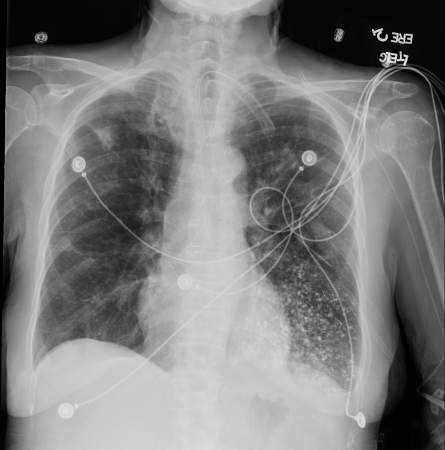

Acute aspiration

Barium aspiration. A barium swallow was conducted in a 53-year-old woman. Imaging revealed hyperdense airway-centered material in the left lower lobe consistent with barium aspiration bronchiolitis. A tracheoesophageal fistula was confirmed

From the collection of Dr Augustine Lee; used with permission of Mayo Foundation for Medical Education and Research, all rights reserved